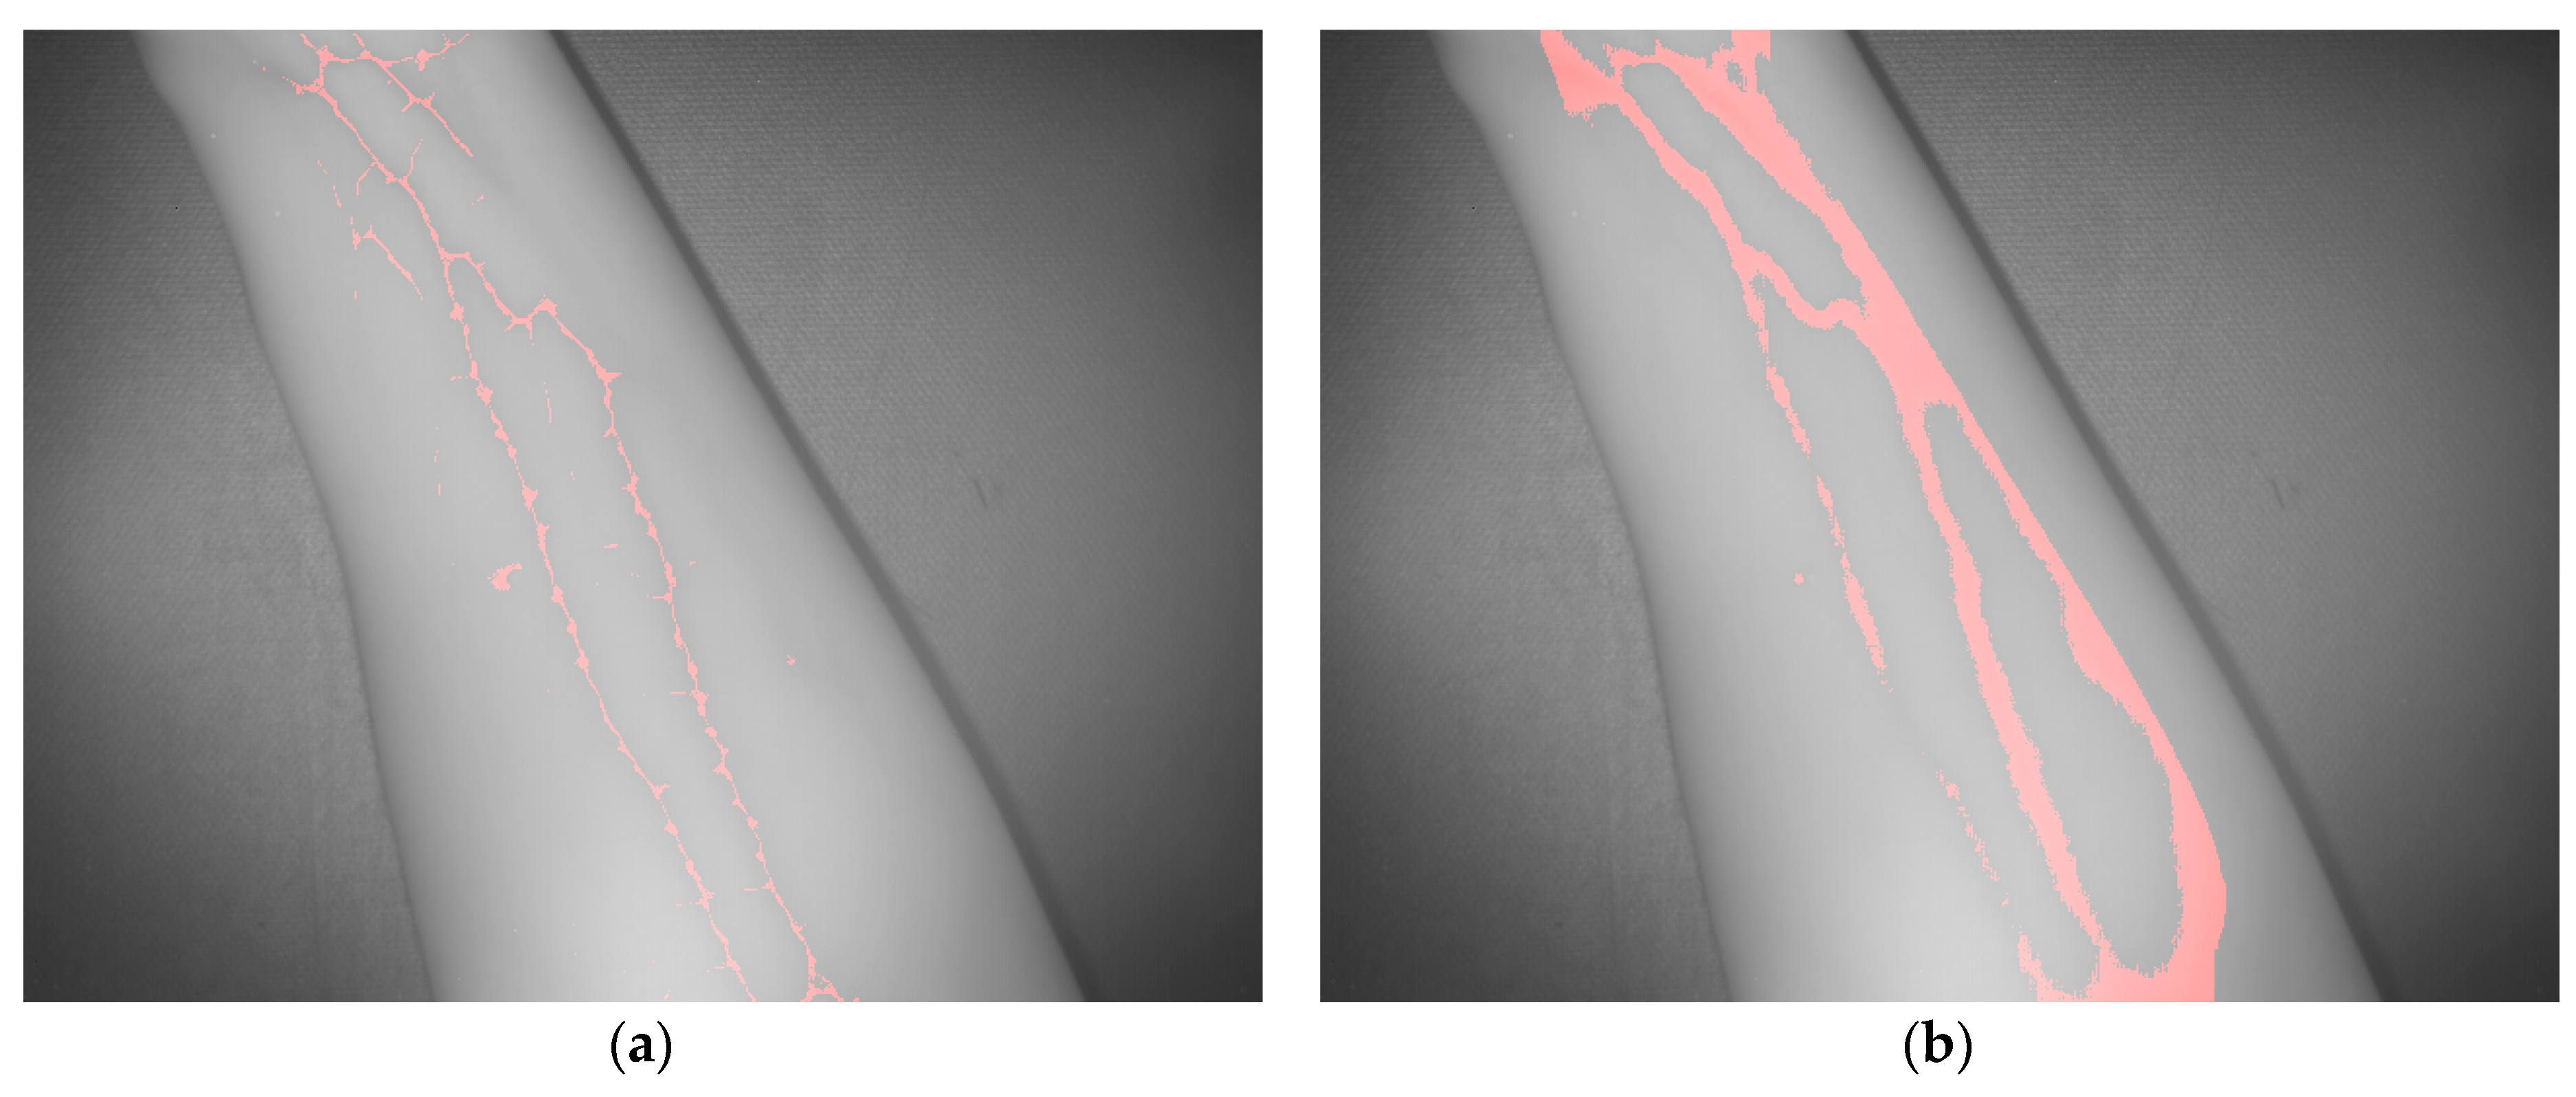

| Test | TP | Accuracy | Error Rate | |

|---|---|---|---|---|

| 1 | Method based on adapted max. curvature | 21.9% | 97.0% | 3.0% |

| Method based on k-means | 86.7% | 96.5% | 3.5% | |

| 2 | Method based on adapted max. curvature | 16.0% | 97.3% | 2.7% |

| Method based on k-means | 72.3% | 97.0% | 3.0% | |

| 3 | Method based on adapted max. curvature | 22.0% | 97.1% | 2.9% |

| Method based on k-means | 80.9% | 96.1% | 3.9% | |